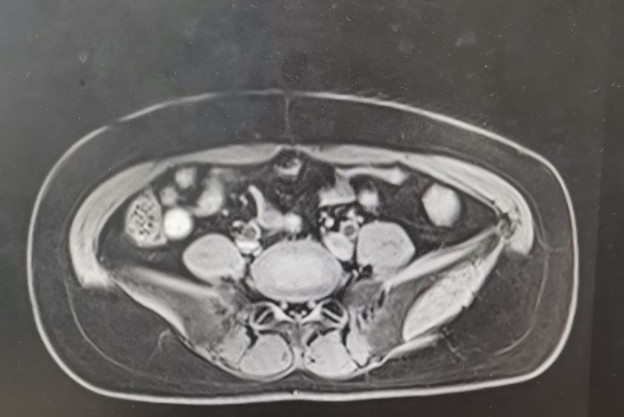

•全腹核磁:子宫术后改变,脂肪肝,双肾囊肿,盆腔少量积液。

轴位T1

轴位T2

矢状位T1

矢状位T2